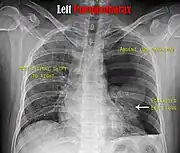

Chest X-ray

A plain chest radiograph, ideally with the X-ray beams being projected from the back (posteroanterior, or "PA"), and during maximal inspiration (holding one's breath), is the most appropriate first investigation.[32] It is not believed that routinely taking images during expiration would confer any benefit.[33] Still, they may be useful in the detection of a pneumothorax when clinical suspicion is high but yet an inspiratory radiograph appears normal.[34] Also, if the PA X-ray does not show a pneumothorax but there is a strong suspicion of one, lateral X-rays (with beams projecting from the side) may be performed, but this is not routine practice.[15][19]

Chest X-ray showing a pneumothorax on the right (left in the image), where the absence of lung markings indicates that there is free air inside the chest

Chest X-ray showing the features of pneumothorax on the left side of the person (right in image)

It is not unusual for the mediastinum (the structure between the lungs that contains the heart, great blood vessels, and large airways) to be shifted away from the affected lung due to the pressure differences. This is not equivalent to a tension pneumothorax, which is determined mainly by the constellation of symptoms, hypoxia, and shock.[13]

The size of the pneumothorax (i.e. the volume of air in the pleural space) can be determined with a reasonable degree of accuracy by measuring the distance between the chest wall and the lung. This is relevant to treatment, as smaller pneumothoraces may be managed differently. An air rim of 2 cm means that the pneumothorax occupies about 50% of the hemithorax.[15] British professional guidelines have traditionally stated that the measurement should be performed at the level of the hilum (where blood vessels and airways enter the lung) with 2 cm as the cutoff,[15] while American guidelines state that the measurement should be done at the apex (top) of the lung with 3 cm differentiating between a "small" and a "large" pneumothorax.[35] The latter method may overestimate the size of a pneumothorax if it is located mainly at the apex, which is a common occurrence.[15] The various methods correlate poorly but are the best easily available ways of estimating pneumothorax size.[15][19] CT scanning (see below) can provide a more accurate determination of the size of the pneumothorax, but its routine use in this setting is not recommended.[35]